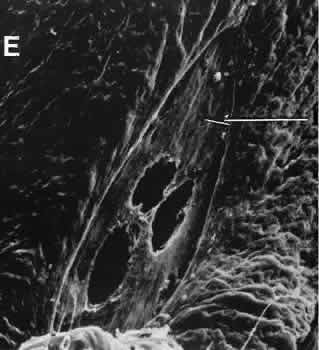

Fig. 40. A case of suspected fungal endophthalmitis following cataract extraction. A. Well-demarcated, globular, opaque masses have developed over a period of weeks in the anterior chamber of a patient who had undergone cataract extraction. The lack of acute inflammatory activity, such as hypopyon formation, suggests a fungal infection. B. The anterior chamber reaction consists of a chronic inflammatory infiltrate characterized by multiple epithelioid histocytes, that is, a granulomatous inflammatory reaction consistent with fungal infection. (Hematoxylin-eosin stain; × 75.) C. A stain for fungus, however, does not reveal the presence of fungal forms. The material does stain with the silver stain, but the morphology is not that of a fungus. The features of the material suggest the inclusion of foreign material. (Gomori methenamine silver stain; × 75.) D. The material in the granulomatous inflammatory infiltrate appears to have a refractile nature when viewed at high magnification. (Hematoxylin-eosin stain; × 300.) E. The definitive test for foreign material is examination by polarized light. Under these conditions, the material can be identified as fibrous material consistent with cotton fibers. Cotton was apparently inadvertently introduced at the time of surgery. The inflammatory reaction is attempting to rid the eye of this foreign material, but the reaction is simultaneously destroying delicate ocular tissue. (Polarized hematoxylin-eosin stain; × 75.)